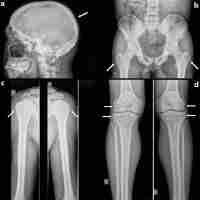

| Abstract | Background and Objective: Severe metabolic complications generally manifest at an early age in Berardinelli – Seip congenital lipodystrophy (BSCL) and their management is especially challenging. Nutritional intervention with low lipid personalized diets is considered by experts to be fundamental in handling the disease when associated with medical therapy, however little is known about the beneficial effects of dietary interventions alone. Aim: To underline the importance of a well-structured low-fat diet in BSCL patients. Methods and Results. A BSCL male patient strictly followed a personalized hypolipemicdiet (60% carbohydrates, 22% fats and 18% proteins) since clinical diagnosis at the age of one year. Interestingly, pharmacological interventions were not required at any point during follow up. Aged 16 years the patient was referred to our centre. Biochemistry, hormonal evaluation, 75 mg oral glucose tolerance test, cardiac evaluation and abdominal ultrasound were performed, revealing no abnormalities. Genetic analysis and leptin dosage were carried out, confirming the diagnosis of BSCL type 1 (homozygosity for c.493-1G>C pathogenic variant in AGPAT2 gene) and showing undetectable circulating levels of leptin (< 0.229 mcg/L). Diet therapy alone was therefore maintained, scheduling follow-up visits every six months, with excellent disease control ever since. Conclusions. This report proves how a personalized low-fat diet is of great help in the management of BSCL and its complications. In addition, a specific hypolipemic diet could be used alone as an effective long-term treatment in selected cases with high compliance and, probably, a milder phenotype. |